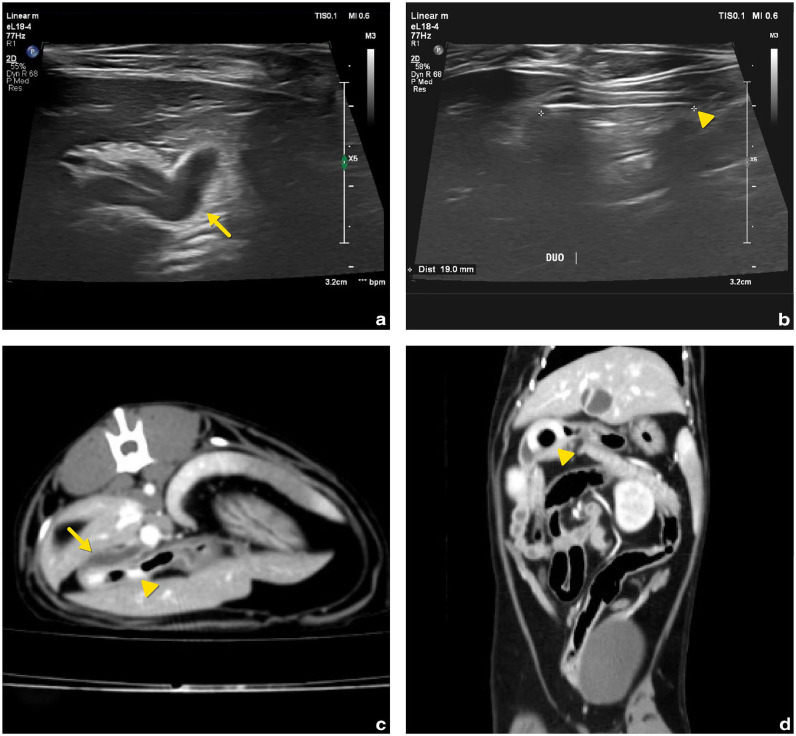

Case summary: A spayed female British Shorthair cat aged 1 year and weighing 2.6 kg presented with a 5-day history of vomiting and anorexia. Physical examination revealed icterus, and serum biochemistry showed markedly elevated bilirubin and liver enzyme levels. Abdominal ultrasonography revealed a dilated common bile duct (4 mm), mild gallbladder wall thickening and a round, hyperechoic foreign body located at the major duodenal papilla. A contrast-enhanced CT scan confirmed the presence of a 1.9 cm doughnut-shaped foreign body in the proximal descending duodenum, causing extramural compression of the common bile duct. Exploratory laparotomy and enterotomy were performed to remove the object. The cat recovered uneventfully, with normalisation of biliary parameters within 48 h and resolution of clinical signs by postoperative day 4.

Relevance and novel information: This case highlights a rare but surgically treatable cause of extrahepatic biliary obstruction (EHBO) in cats caused by a duodenal foreign body exerting extraluminal compression without intraluminal migration or mucosal invasion. It emphasises the value of cross-sectional imaging and timely surgical intervention in achieving favourable outcomes. To the authors' knowledge, this is the first peer-reviewed report of feline EHBO caused by extramural duodenal compression that was successfully resolved without biliary tract incision.